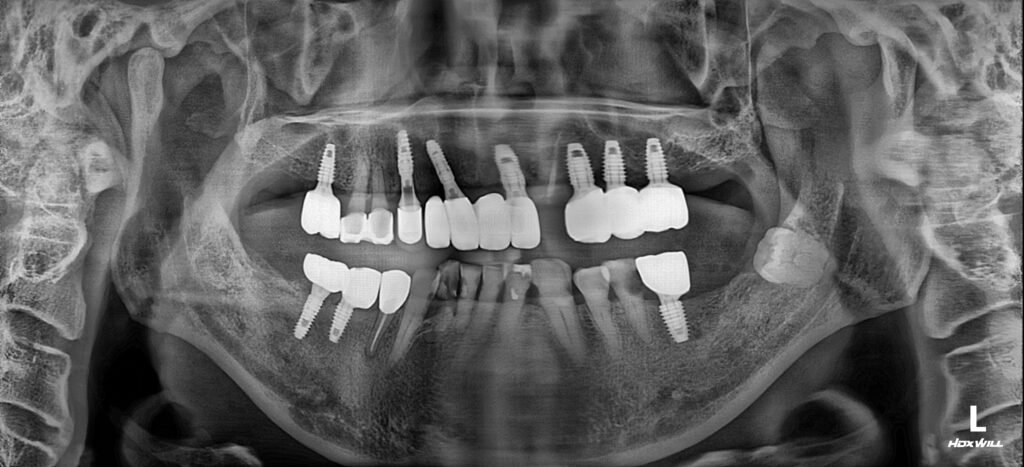

26.02.26

초기에 치료 목표로한 임플란트와 신경치료를 성공적으로 마무리한 모습입니다!

환자분께서 자신의 사정을 세심하게 배려하여 모든 일정과 치료를 진행한 서울 화이트S치과에 고마움을 말씀주시며, 앞으로 남은 치료도 믿고 진행하시겠다고 하셨습니다.